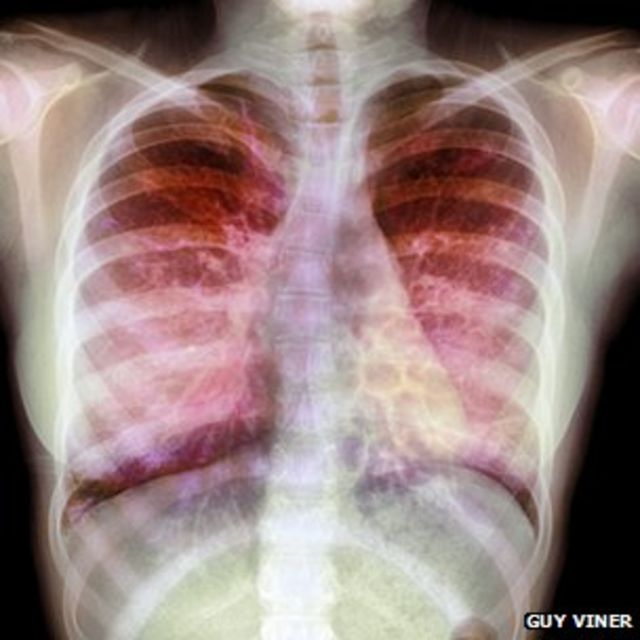

A fibrose cística é uma enfermidade rara que aumenta a produção de muco nos pulmões e atrapalha a respiração. O Trikafta é o único capaz de diminuir os efeitos da doença – com valor de cerca de R$ 2 milhões por ano.